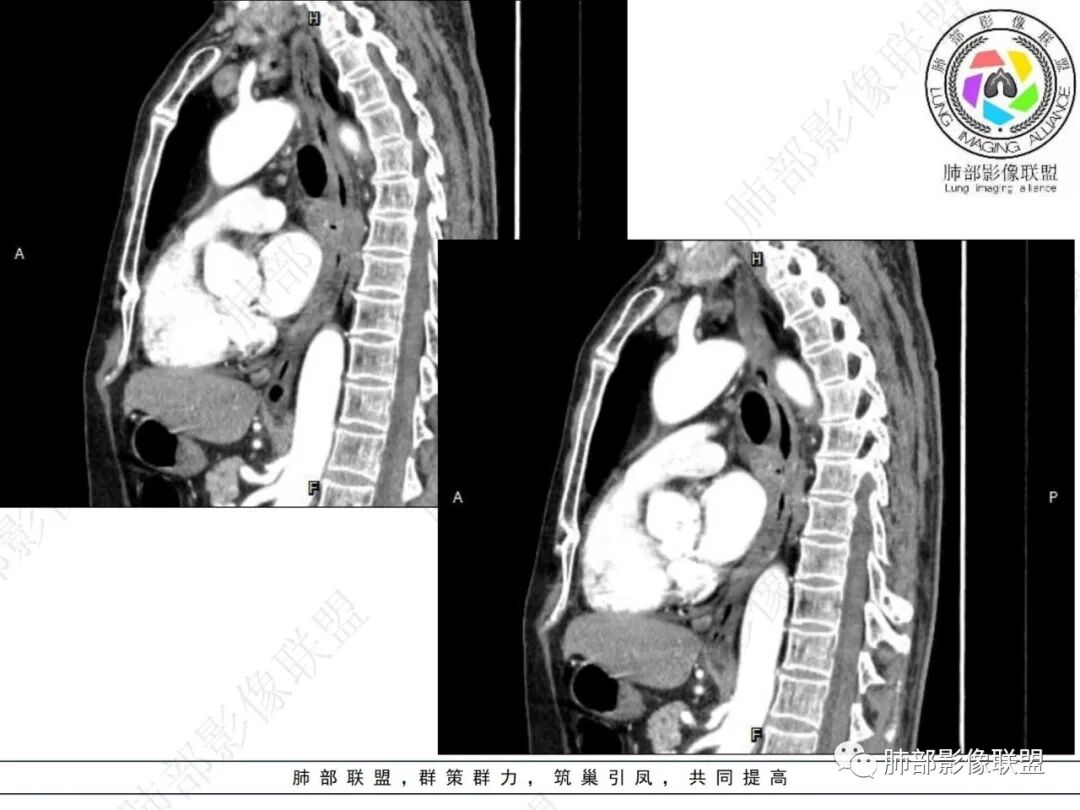

右肺下叶沿肺叶肺段分布斑片、条片状影,以下叶背段为显,边缘模糊,内可见支气管走行,局部支气管管壁增厚,右侧胸腔少量积液。纵隔隆突下可见不均匀软组织密度影,与周围结构分界不清,内见气体密度影,与食管及相邻右肺支气管之间未显示通道。邻近食管下段壁明显不规则增厚,增强后食管管壁明显不均匀强化,可见线样强化的连续完整粘膜影。

3.综合分析:

右肺下叶片影,气道相关,符合感染性病变。纵隔隆突下软组织密度影,异常气体影,长病程,起病缓慢,提示存在气管或食管瘘。食管镜未见明显新生物形成,临床未提供进食或饮水呛咳临床表现,综合分析应该考虑支气管瘘的形成。

对比患者3月份的CT图,原隆突下存在增大钙化淋巴结,现在出现气体影,且钙化显示不清,应想到淋巴结结核破溃成瘘可能性。

这个病例提示我们纵隔内淋巴结伴钙化或肺内结核伴钙化,可能会因患者的免疫力下降使结核复燃。